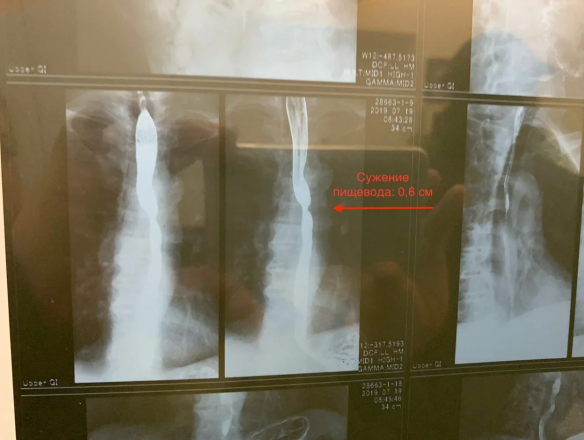

Врачи НИИ имени Н. В. Склифосовского диагностировали у продюсера Бари Алибасова сильное сужение пищевода до 0,6 см. При этом еще в начале июля обследование показало сужение до 0,8 см. Также у него диагностирован эзофагит, гастрит, дуоденит и дуодено-гастральный рефлюкс

"По причине серьезного сужения пищевода артист может принимать пищу исключительно в жидком виде. Даже таблетки приходится дробить на части, чтобы они не застряли при приеме. Бари Каримович сильно похудел", – рассказал помощник продюсера Вадим Горжанкин.